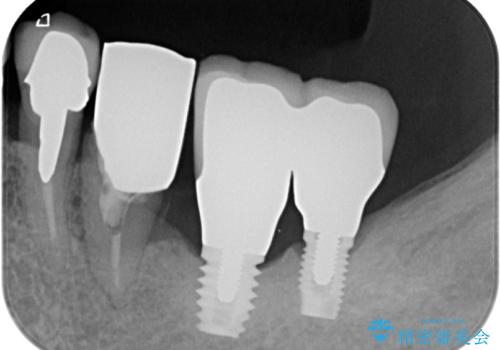

強い咬合力で歯が割れる 奥歯を1DAYインプラントで短期間治療

- 奥歯が割れてしまい、抜歯が必要となった患者様です。

以前にも歯が割れてインプラント治療を行いましたが、抜歯してからインプラント埋入→仮歯装着までに半年以上を要し、その間に残された歯への負担が大きくなり、左右反対側のセラミッククラウンが破折したことがありました。

そのため、当院に新しく導入した手法により、抜歯をした日にインプラントを埋入し、そのままを仮歯を装着することで、他の歯への負担を軽減する計画を立てました。

インプラント埋入時に植立具合の安定性を測定したところ、十分な数値が得られたため、速やかに仮歯を装着して咬合回復をさせることができました。

抜歯を含めた外科処置を1回に抑えることができ、あっという間に治療を終えることができました。